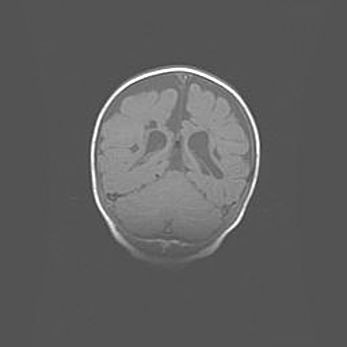

Неполная лизэнцефалия (пахигирия). Открытая гидроцефалия.

Возраст: 17 дней

Вес: 3110 г

Пол: мужской

Окружность головы: 33,5 см

Срок гестации: 35-36 недель

Лизэнцефалия—недоразвитие корковой пластинки и мозговых извилин в результате нарушения миграции нейронов коры. Поверхность мозговых полушарий гладкая. Микроскопически выявляется отсутствие нормальных слоев коры и скопление групп нейронов в подкорковом белом веществе.

Пахигирия—уменьшение числа вторичных извилин. В пораженном полушарии нервные клетки образуют толстый недифференцированный слой с неправильно расположенными нервными волокнами и группами гетеротопных клеток. Нервные клетки незрелые. Белое вещество истончено. При этом нередко аномально развит корково-спинномозговой путь.